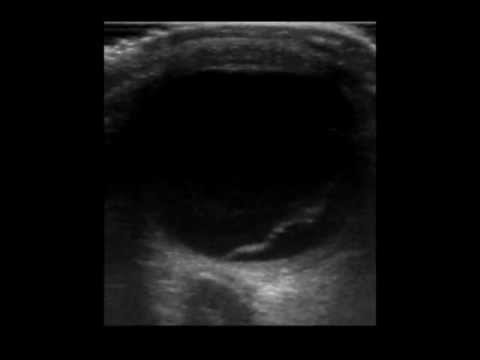

Tethered Retinal Detachment On Point Of Care Ultrasound Pocus Retinal Detachments Are Tethered

The Detached Retina Appears As A Thick Hyperechoic Band In The Vitreous